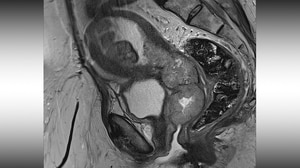

Diagnosis and Treatment of Cervical CancerCervical cancer is the fourth most common cancer worldwide and is the 20th most common cancer in the United States, with an estimated 13,820 new cases and 4360 deaths in 2024.